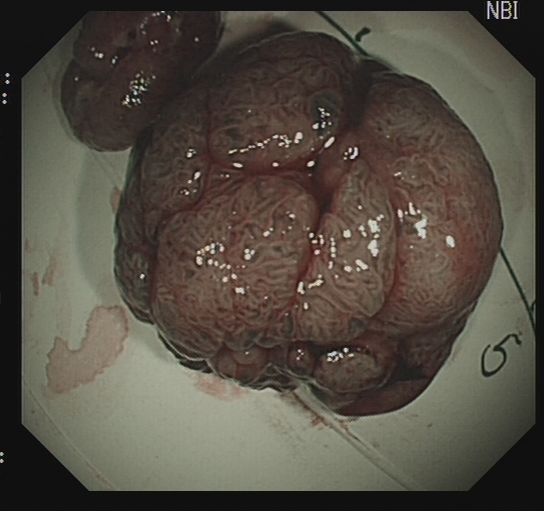

结肠息肉的治疗方法主要包括内镜下治疗外科手术治疗及术后随访内镜下治疗高频电切术是常用方法,利用高频电流热效应使息肉组织凝固坏死脱落有蒂息肉采用圈套器圈套后电切无蒂小息肉用黏膜切除术EMR较大无蒂息肉需黏膜下剥离术ESD,可完整切除并病理分析儿童需严格评估息肉情况及耐受。

结肠息肉的治疗主要包括内镜下治疗外科手术治疗以及术后随访一内镜下治疗1高频电切术适用于直径较小一般小于2cm的有蒂息肉通过高频电流产生的热效应,使息肉组织凝固坏死并脱落,操作简便且切除效果确切该方法能有效降低复发风险,但需谨慎评估合并严重心肺疾病等基础疾病的患者,因手术。